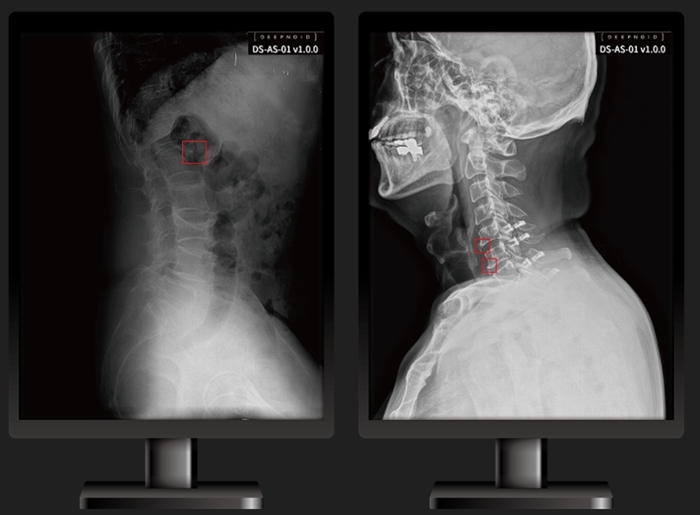

의료 인공지능(AI) 플랫폼 기업 딥노이드(대표이사 최우식)는 척추부위 의료영상 AI 솔루션 '딥스파인(DEEP:SPINE, 모델명 DS-AS-01)'이 식품의약품안전처로부터 의료영상분석 소프트웨어 인증을 획득했다고 3일 밝혔다.

‘딥스파인’은 척추부위를 측정하는 의료영상분석 소프트웨어로 척추, 관절 등 진료를 보조하는 소프트웨어다.

특히 척추는 초기 X-Ray 상에서는 이상 소견을 발견하지 못하는 경우도 있어 병원을 찾아가도 대부분 허리 디스크부터 의심하게 되는데, MRI 같은 영상 검사로도 찾아내기가 쉽지 않아 척추 조기진단을 보조할 것으로 예상된다.